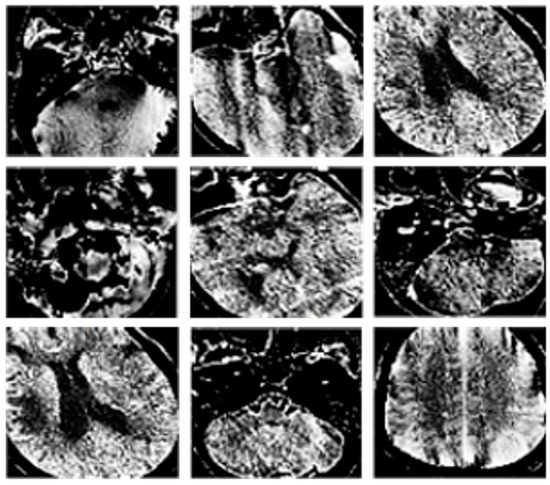

A comparison between the CT image processing that can be achieved through image enhancement methods and the original CT image is shown in Figure 2. Specifically, Figure 2a represents the original image, while Figure 2b represents the artifact image after feature enhancement.

The comparison between the original and enhanced image shows that the proposed image enhancement method can effectively extract artifact region information while weakening irrelevant region information such as bones, providing data support for the subsequent classification task.

Figure 2. Comparison of enhanced and initial image. (a) represents the original image, while Figure (b) represents the artifact image after feature enhancement.